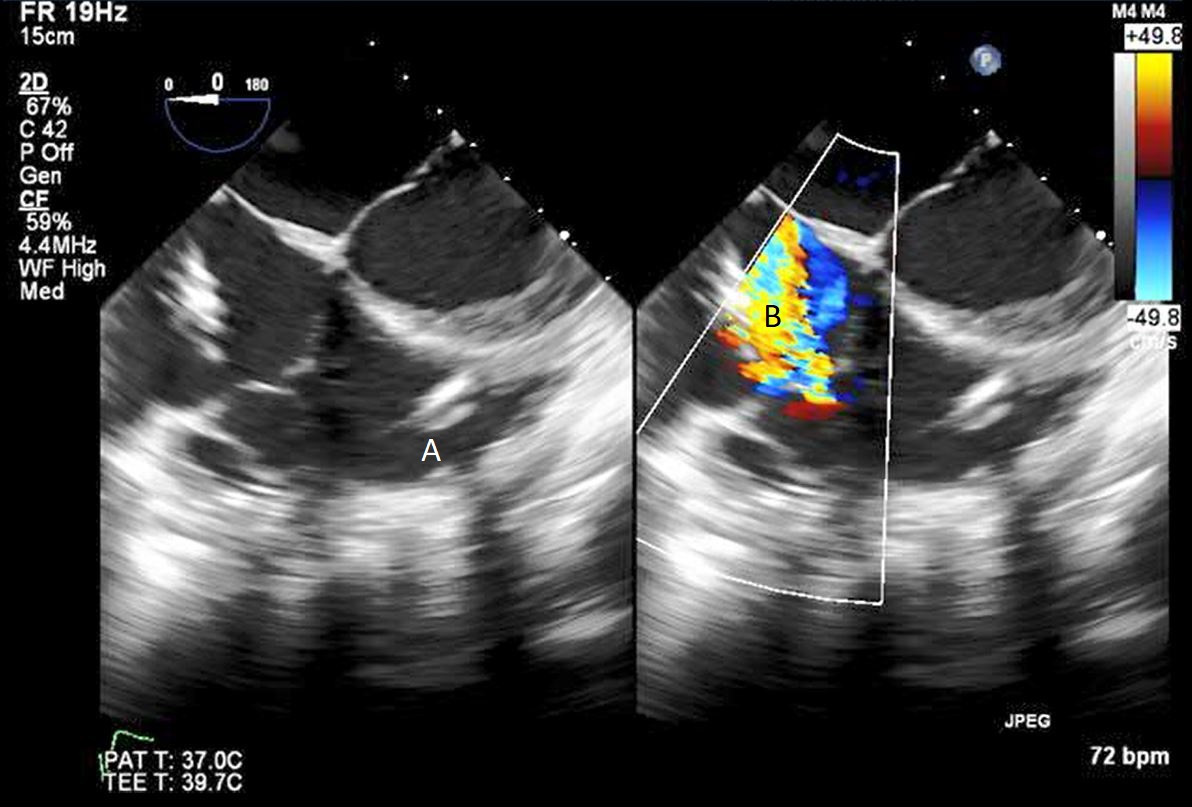

The intra-aortic balloon pump is a percutaneously placed counter pulsation device which helps in decreasing afterload as well as augmenting coronary perfusion. Initially developed in the 1960s it is the oldest MCS device and given its simplicity, cost effectiveness, and ease to implant and explant, it is the most commonly used temporary support device [6]. Although it is typically placed in the cardiac catheterization lab under fluoroscopic guidance, TEE can be utilized to help in its placement in the intubated patient in the intra-operative setting. The femoral artery is the most common site of placement however they can on occasion be placed in alternative sites such as the axillary artery or directly into the aorta [7, 8]. When placed via the femoral artery, it is threaded over a guidewire. TEE can be used to visualize both the guidewire as well as the tip of the IABP catheter during placement (Fig. 1) [9]. Ideal positioning of the balloon tip is 1–2 cm distal to the left subclavian artery to derive maximal hemodynamic benefit [10]. Positioning can be confirmed by visualizing the descending aorta and then withdrawing the TEE probe until the left subclavian artery and aortic arch are visualized. Upon activation of the balloon pump the gas filled balloon will cause shadowing and reverberation artifacts (Fig. 2). Its presence can be used as confirmation of proper function of the device. If these artifacts are not seen or bubbles are visualized in the aorta, rupture of the IABP should be suspected [9]. In addition to hemodynamic monitoring with a Swan-Ganz catheter, TTE can be used to monitor LV function after IABP placement and can help guide weaning of IABP support. It can also visualize any new or worsening aortic regurgitation. Given that IABPs work by reducing afterload, on rare occasions they can precipitate dynamic outflow tract obstruction and paradoxically worsen cardiogenic shock. Examples include patients with a relatively preserved basal or septal myocardial function in scenarios such as takotsubo cardiomyopathy or acute myocardial infarctions. Doppler imaging and color flow doppler can be used to identify such scenarios [11].

Fig. 1.TEE demonstrating IABP in descending aorta (A).

TEE demonstrating IABP in descending aorta (A) with reverberation artifact seen behind it upon activation (B).